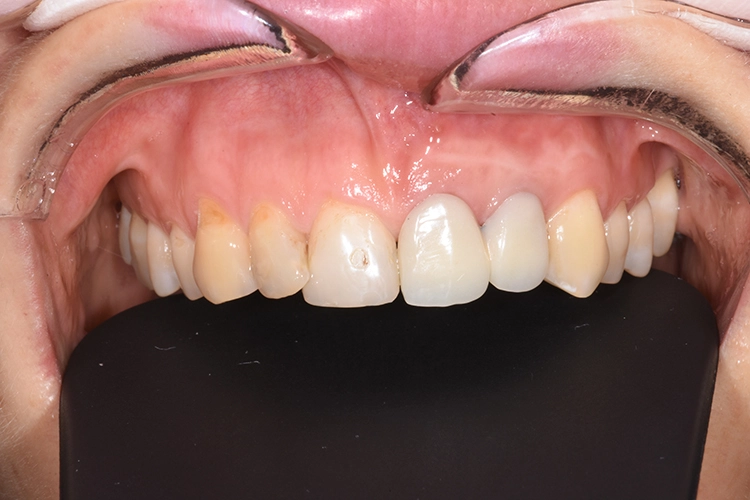

Zu unserem Ausgangsbefund zählt die sechs Punkt-Taschenmessung, die Vitalität und Perkussionsprobe sowie ein Röntgenbild. Besonders wichtig ist in diesem Zusammenhang auch die genaue Anamnese des Patienten.

Dr. Blume

Deutlich auffallend und für die Patientin sehr wichtig war die anatomisch individuelle Zahnstellung des Zahnes 11. Um dem Wunsch der Patientin auf eine für ihr Umfeld unauffällige Behandlung gerecht zu werden, entschieden wir uns gemeinsam für eine Sofortimplantation mit einer provisorischen Sofortversorgung des Implantates. Kein Provisorium kommt der Natur so nah wie die Natur selbst und daher planten wir die Umarbeitung der Zahnkrone 11.